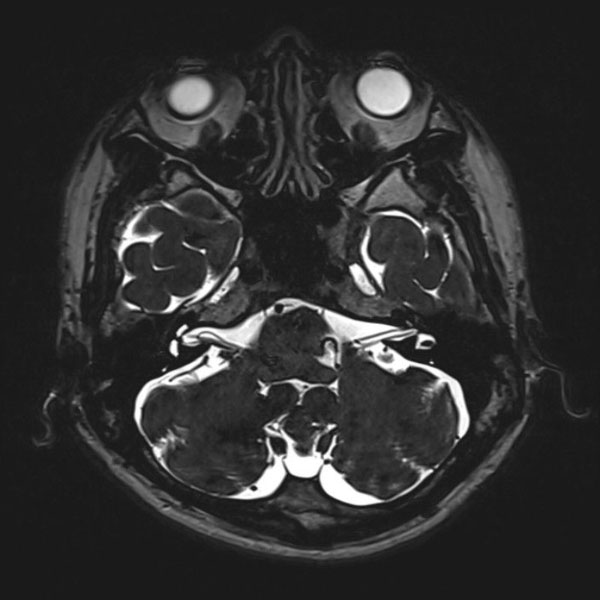

手術前

(MR1)

手術後

(CT)